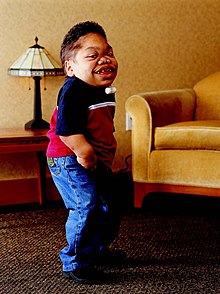

قیمت: 52٬500 تومان - دسته بندی فایل: پاورپوینتدانلود پاورپوینت مطالعه سندروم پرادر ویلی

جدیدترین و ارزانترین فایل پاورپوینت با عنوان پاورپوینت مطالعه سندروم پرادر ویلی تعداد اسلاید: 28